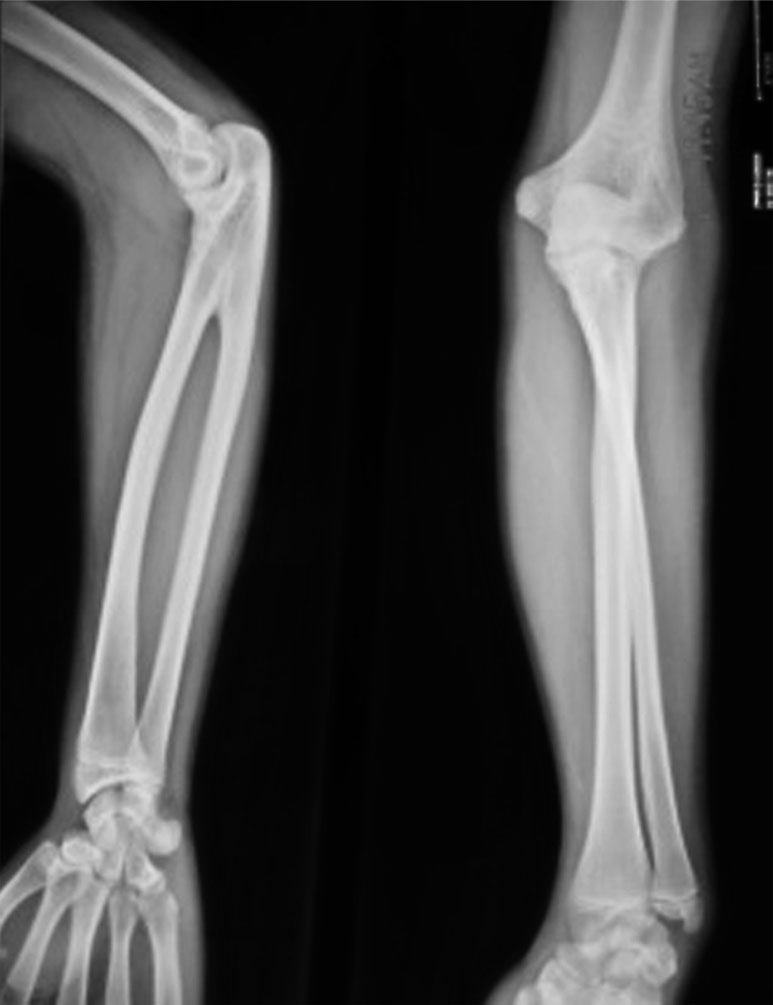

X 线正位片(A)和侧位片(B)显示右侧前臂肱桡骨骨性融合,合并尺骨发育不良

图1-2-20 肱骨桡骨骨性融合病例